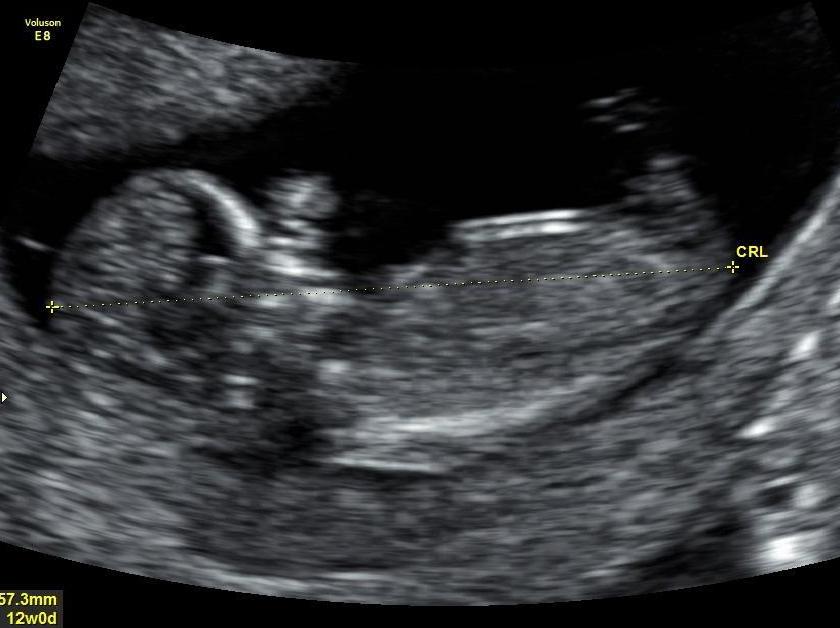

Hello All :) Last time I post this promise im just so excited to find out the gender.. Are there any Guesses on my babys 12 week ultrasound?? Il be sure to post the update on gender in here once I find out :) :)

Attachment 17439Attachment 17440Attachment 17441